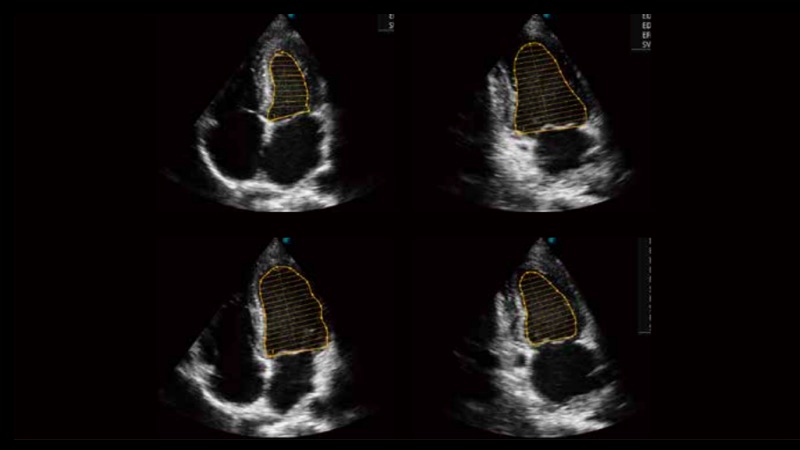

To recognize myocardial intima during diastolic and systolic period and calculates the ejection fraction automatically.